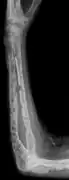

Bone pain

Bone pain affects almost 70% of people with multiple myeloma and is one of the most common symptoms.[2]:653[22] Myeloma bone pain usually involves the spine and ribs, and worsens with activity. Persistent, localized pain may indicate a pathological bone fracture. Involvement of the vertebrae may lead to spinal cord compression or kyphosis. Myeloma bone disease is due to the overexpression of receptor activator for nuclear factor κ B ligand (RANKL) by bone marrow stroma. RANKL activates osteoclasts, which resorb bone. The resultant bone lesions are lytic (cause breakdown) in nature, and are best seen in plain radiographs, which may show "punched-out" resorptive lesions (including the "raindrop" appearance of the skull on radiography). The breakdown of bone also leads to the release of calcium ions into the blood, leading to hypercalcemia and its associated symptoms.[23]